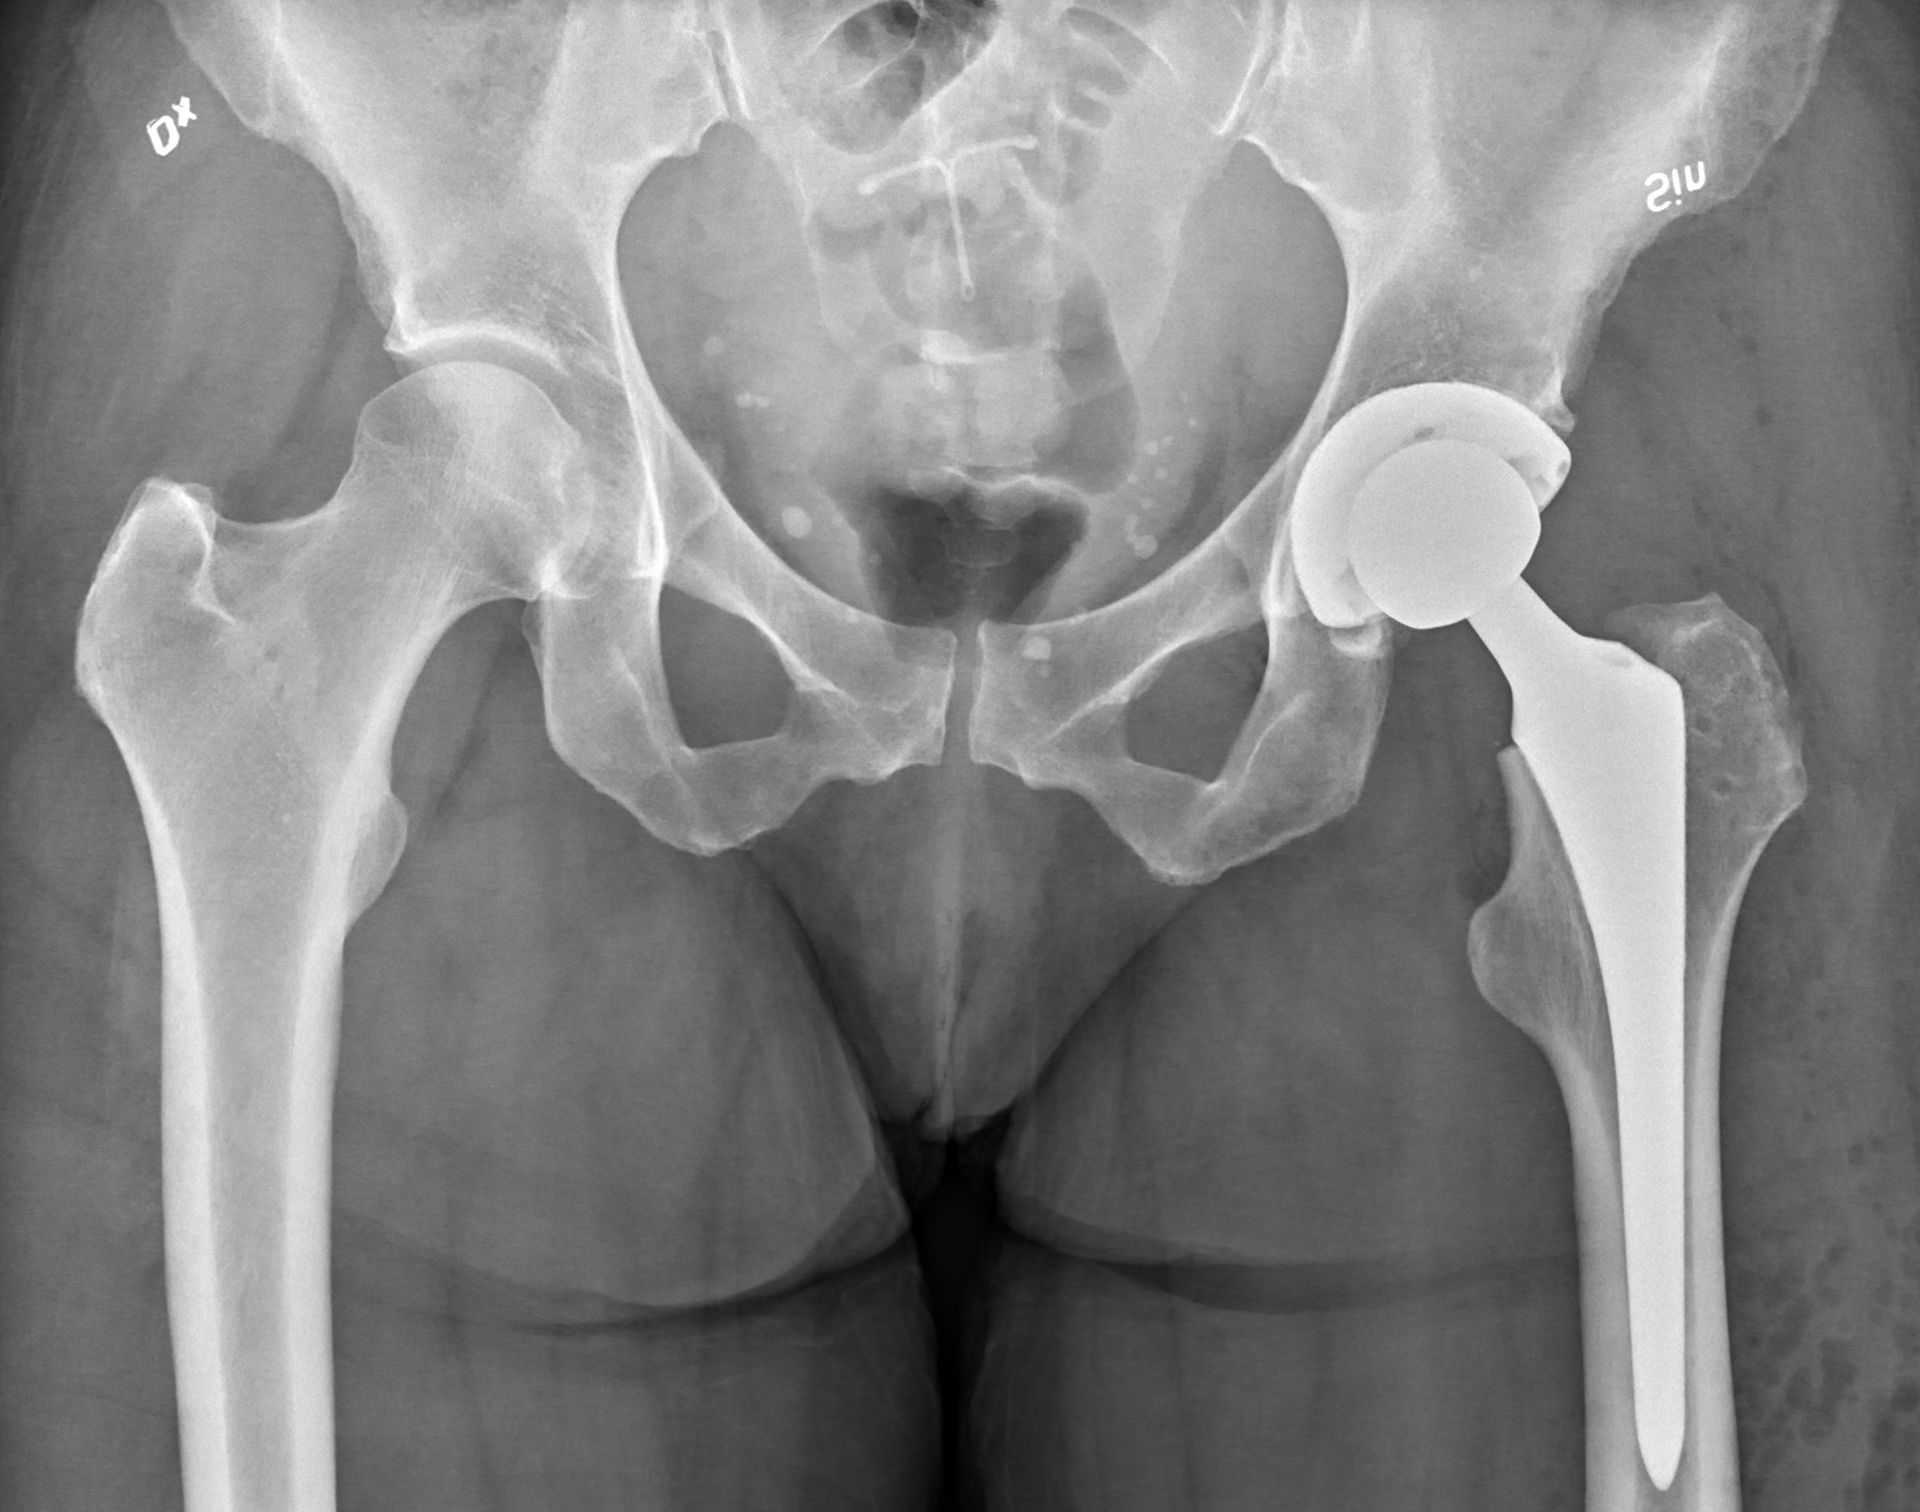

Prótese total de quadril não cimentada. Dor e atrose no quadril

Por thiagoaugustomh 31 de outubro de 2025

Saiba como é feita a cirurgia de prótese de quadril, quando é indicada e como é a recuperação. Atendimento especializado em Campinas e região.